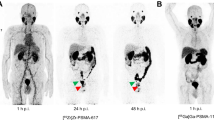

Of altogether 20 lesions considered to be indeterminate for prostate cancer on [68Ga]Ga-PSMA-11 PET/CT, 6 (30%) were classified as suspicious (positive) and the remaining 14 (70%) as non-suspicious (negative) on [89Zr]Zr-PSMA-617 PET/CT. Figure 1 shows [89Zr]Zr-PSMA-617 PET/CT images at 1 h, 24 h, and 48 h post-injection, and the corresponding [68Ga]Ga-PSMA-11 PET/CT scan 1 h post-injection from a patient whose indeterminate lesion was confirmed to be suspicious (positive) on [89Zr]Zr-PSMA-617 PET/CT; also illustrated is a quantitative analysis of this lesion.

Maximum intensity projection (MIP) images of a patient with biochemical recurrence of prostate cancer on A) [68Ga]Ga-PSMA-11 PET/CT 1 h post-injection and B) (right to left) [89Zr]Zr-PSMA-617 PET/CT 1 h, 24 h, and 48 h post-injection. As denoted by the red arrows, a lesion faintly visible on the [68Ga]Ga-PSMA-11 scan, although not clearly discernible on the 1-hr [89Zr]Zr-PSMA-617 image, was clearly discernible as a presumed bone metastasis on the 24-hr and 48-hr [89Zr]Zr-PSMA-617 scans. Supporting the visual findings, [89Zr]Zr-PSMA-617 uptake, reflected by C) the SUVmax curve for the lesion, showed a sharp increase from 1 to 24 h, and then a slower increase from 24 to 48 h